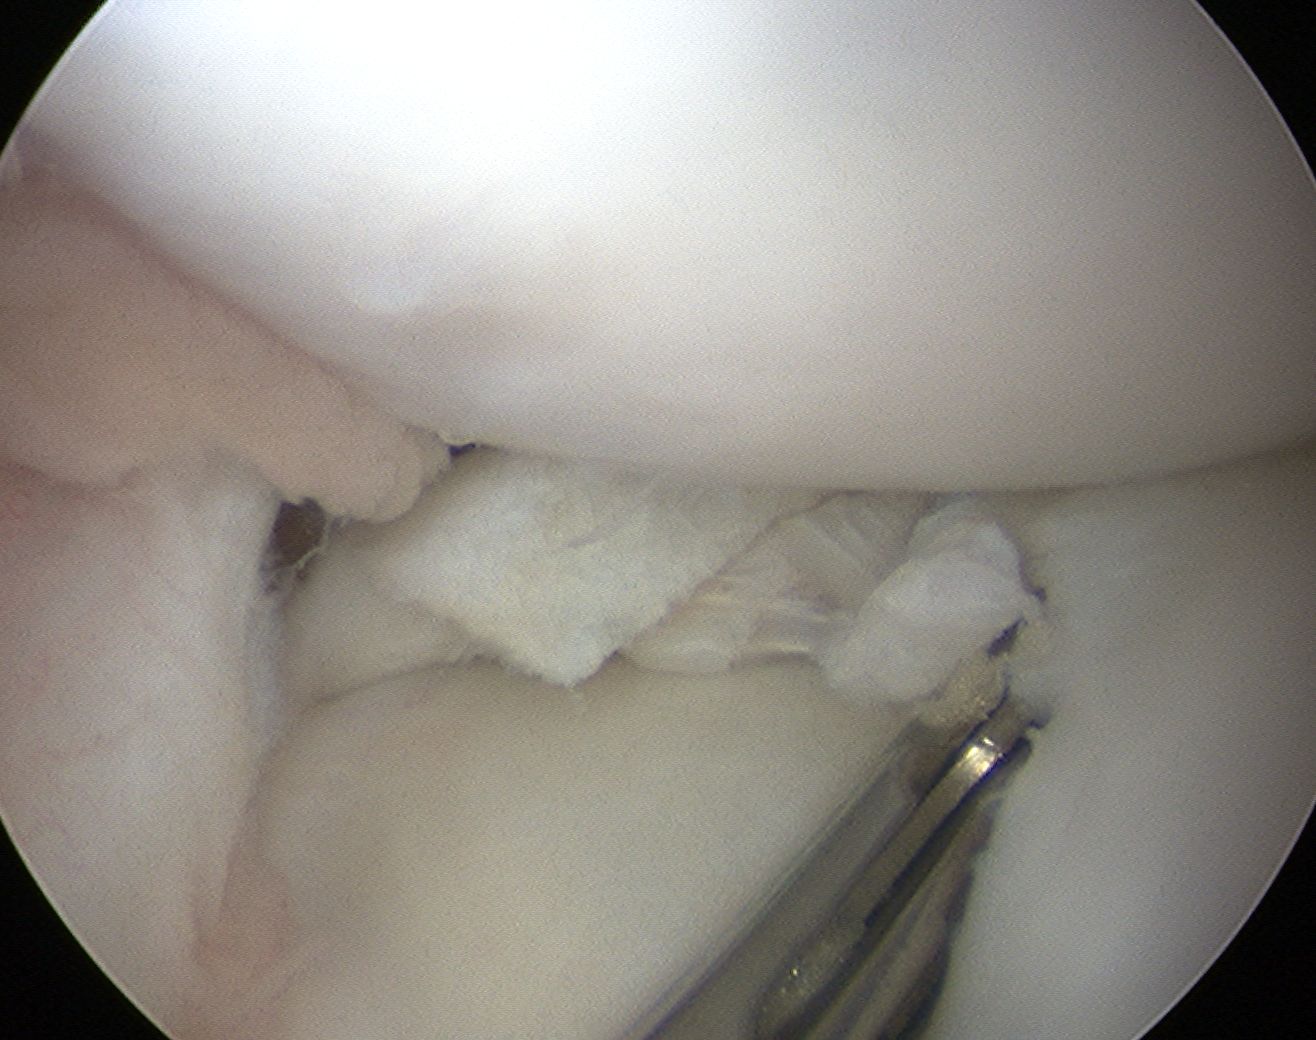

Aim

Convert unstable meniscus to a stable contoured one

Options

1. Stable

- partial central meniscectomy / saucerisation

Technique Saucerisation

Technique

- make incision with scissors in medial aspect

- resect posterior part

- saucerise laterally and anteriorly

- need to ensure don't detach anterior horn